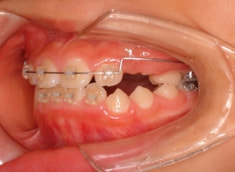

治療開始から3ヶ月後

治療開始して3ヶ月で前歯はジャンプしておりますが、フェイスマスクをこの後もしっかり使用していただくことが大切です。

まだ治ったわけではないのです。